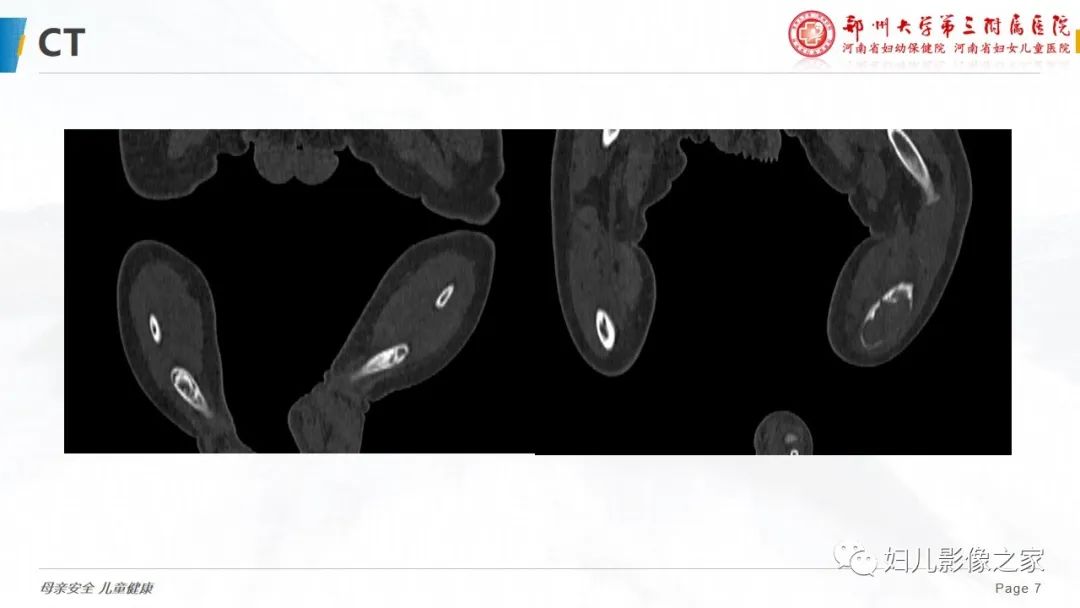

【PPT】骨纤维结构不良-7